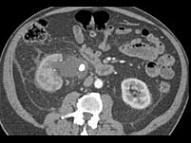

男,27岁,请根据所示图像,选择最可能诊断 ( )A、右肾结石B、右肾钙化C、右侧肾盂结石D、右侧肾盂癌E、右侧肾盂血块

问题 男,27岁,请根据所示图像,选择最可能诊断 ( )

选项 A、右肾结石 B、右肾钙化 C、右侧肾盂结石 D、右侧肾盂癌 E、右侧肾盂血块

答案 C